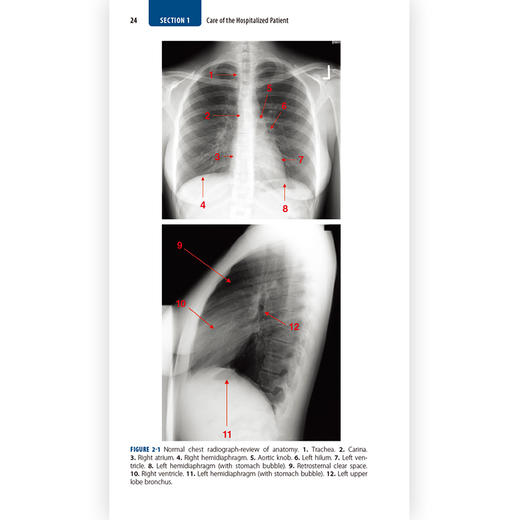

2 Diagnostic Imaging in Internal Medicine..................................23